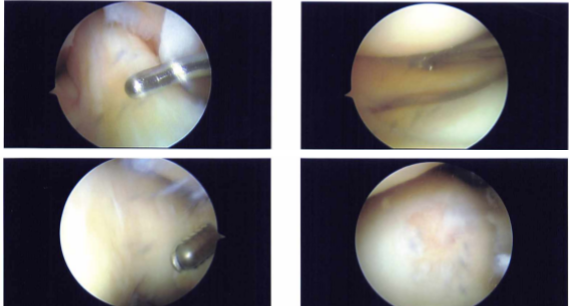

A sharp knife was used to make a lateral portal incision. A spinal needle and knife were used to create a medial portal. A vertical, nearly complete rip in Zone 3 surrounding the meniscus’s body was visible upon examination of the medial compartment.

In order to execute a partial meniscectomy, biters and a shaver were used. The medial femoral condyle’s weight-bearing portion had a Grade III to Grade IV lesion, measuring around 1 cm in diameter, according to a cartilage examination.

With the aid of a shaver, this was debrided, and the shaver was then used to execute an abrasion chondroplasty. The infrapatellar notch examination revealed an undamaged ACL. The meniscus and cartilage in the lateral femoral compartment were in good condition.

When the trochlea was removed, an examination of the patellofemoral compartment revealed Grade I arthritic alterations. The patella’s articular structure remained unchanged.

Intraoperative Images